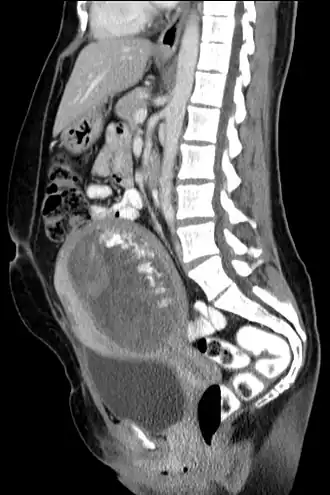

| Tomografia computadorizada, vista sagital. | |